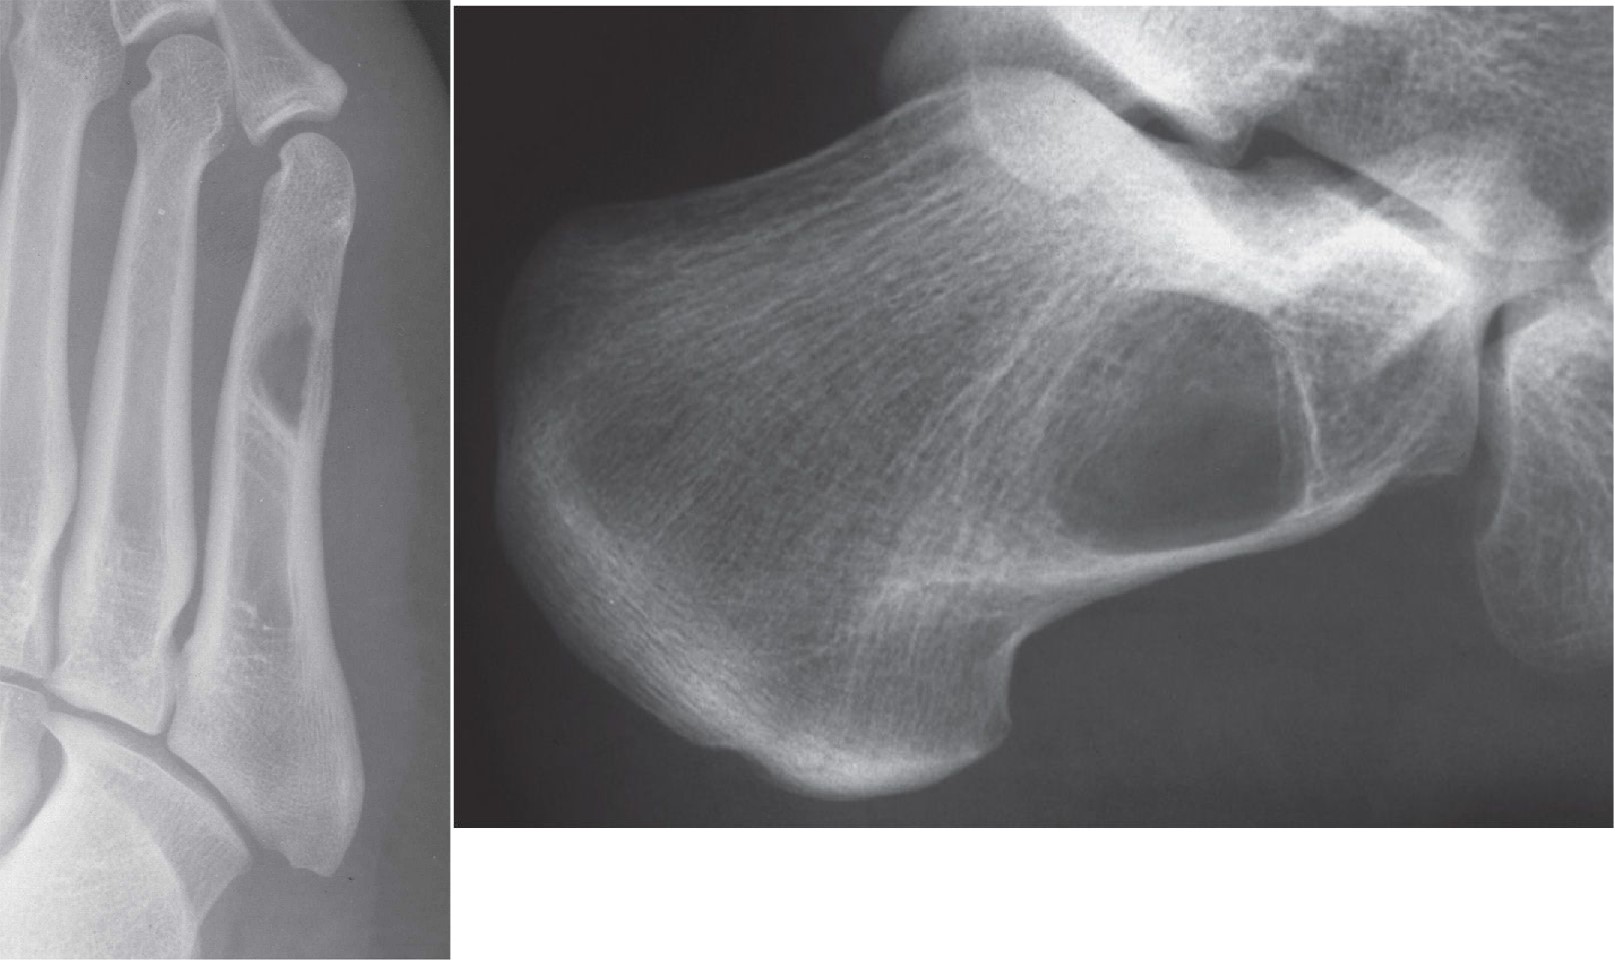

A 68 year old lady presented to an orthopedician at a different centre...

Read More